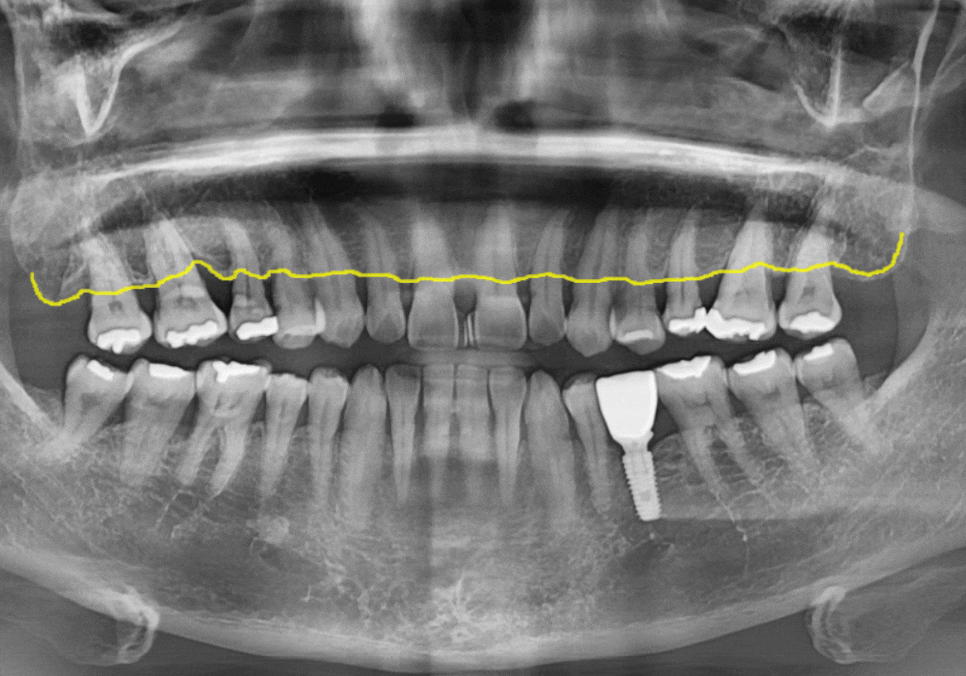

우리 치아는

겉을 감싸는 하얀 법랑질(enamel)과

그 안쪽의 노란빛을 띄는 상아질(dentin)로

이루어져 있습니다.

고덕동 치과 누런 이, 앞니 사이 틈, 잘못된 관리 때문일까?

법랑질은 우리 몸에서

가장 단단한 조직이지만,

평생 수천 번의 저작 운동과

음식, 생활 습관, 외부 자극을 반복적으로 받으며

조금씩 마모될 수밖에 없습니다.

이 과정에서

법랑질의 두께가 얇아지면

안쪽의 상아질 색이 비쳐 보이게 되고,

치아는 점점

어둡고 누렇게 보이게 됩니다.

이처럼 노화로 인한 치아 변색은

표면 착색과는 원인이 다르기 때문에

전문가 치아미백만으로는

개선이 어려운 경우가 많습니다.